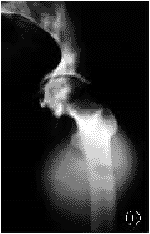

3髋在骨水泥-骨界面间有部分X线透光带,髋臼各区未见明显骨溶解及骨吸收区,无1髋臼假体移位>3mm。依据Hodgkinson标准,无1髋臼假体有肯定松动(图1,2)。

图1左髋骨性关节炎,关节间隙变窄。股骨头呈圆锥形,髋臼内陷凸入盆腔内

图2全髋关节置换术后,髋臼内壁植骨,钛合金网架重建,骨水泥及超高分子聚乙烯髋臼帽置入,髋臼外上缘缺损处植骨,加压螺钉固定